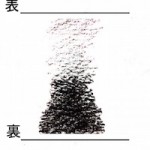

胸脇苦満ノ毒、浅薄ナル者ノ圖也。

按之而知ノ傳、圖ノ如ク、

脇下肋骨ノ端ヲ指ニテカヽゲミルニ、コタユルモノアリ。

是薄キ苦満ノ毒ナリ。

又、心下ヲ按テ少シクコタユルモノナリ。

是即痞鞕ナリ。世二積聚ト号スルモノ、此ノ證多シ。

又圖ノ如ク、苦満アリテ、心下痞硬甚シキモノアリ。

此時ハマヅ苦満ヲサシ置テ、痞鞕ヨリ攻ベシ。

原文の緑の下線部①〜③について

腹部の邪の現れ方についてです。

①厚深ナルモノハ見易ク

(邪が深くにあるものは見やすい)

②浅薄ナルモノハ見難シ。

(邪が浅くにあるものは見難い)

③毒浅薄ナルカ、如クニシテ、大二深キモノアリ。

(邪が浅くにあるようにみえても実は深くにある場合がある)

③は邪が腹底にあり、

表には現れないものである。

と記載されています。